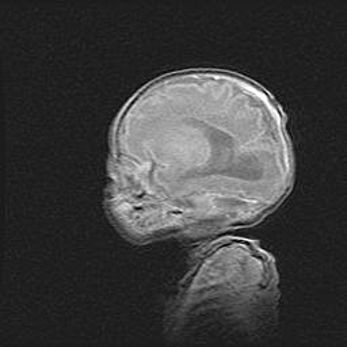

Аномалия Денди-Уокера. Признаки гипоплазии мозолистого тела.

Возраст: 5 месяцев 3 дня

Вес: 5550 г

Пол: мужской

Окружность головы: 39 см

Срок гестации: 40 недель

Аномалия Денди-Уокера – это порок развития головного мозга, для которого характерна триада симптомов: гипотрофия или аплазия червя мозжечка и/или полушарий мозжечка, расширение четвёртого желудочка с формированием ликворной кисты задней черепной ямки, гипертензионная гидроцефалия различной степени.

Гипоплазия мозолистого тела относится к дефектам внутриутробного этапа развития мозговой ткани, возникающим в процессе закладки структур головного мозга, что происходит на начальных этапах развития эмбриона.